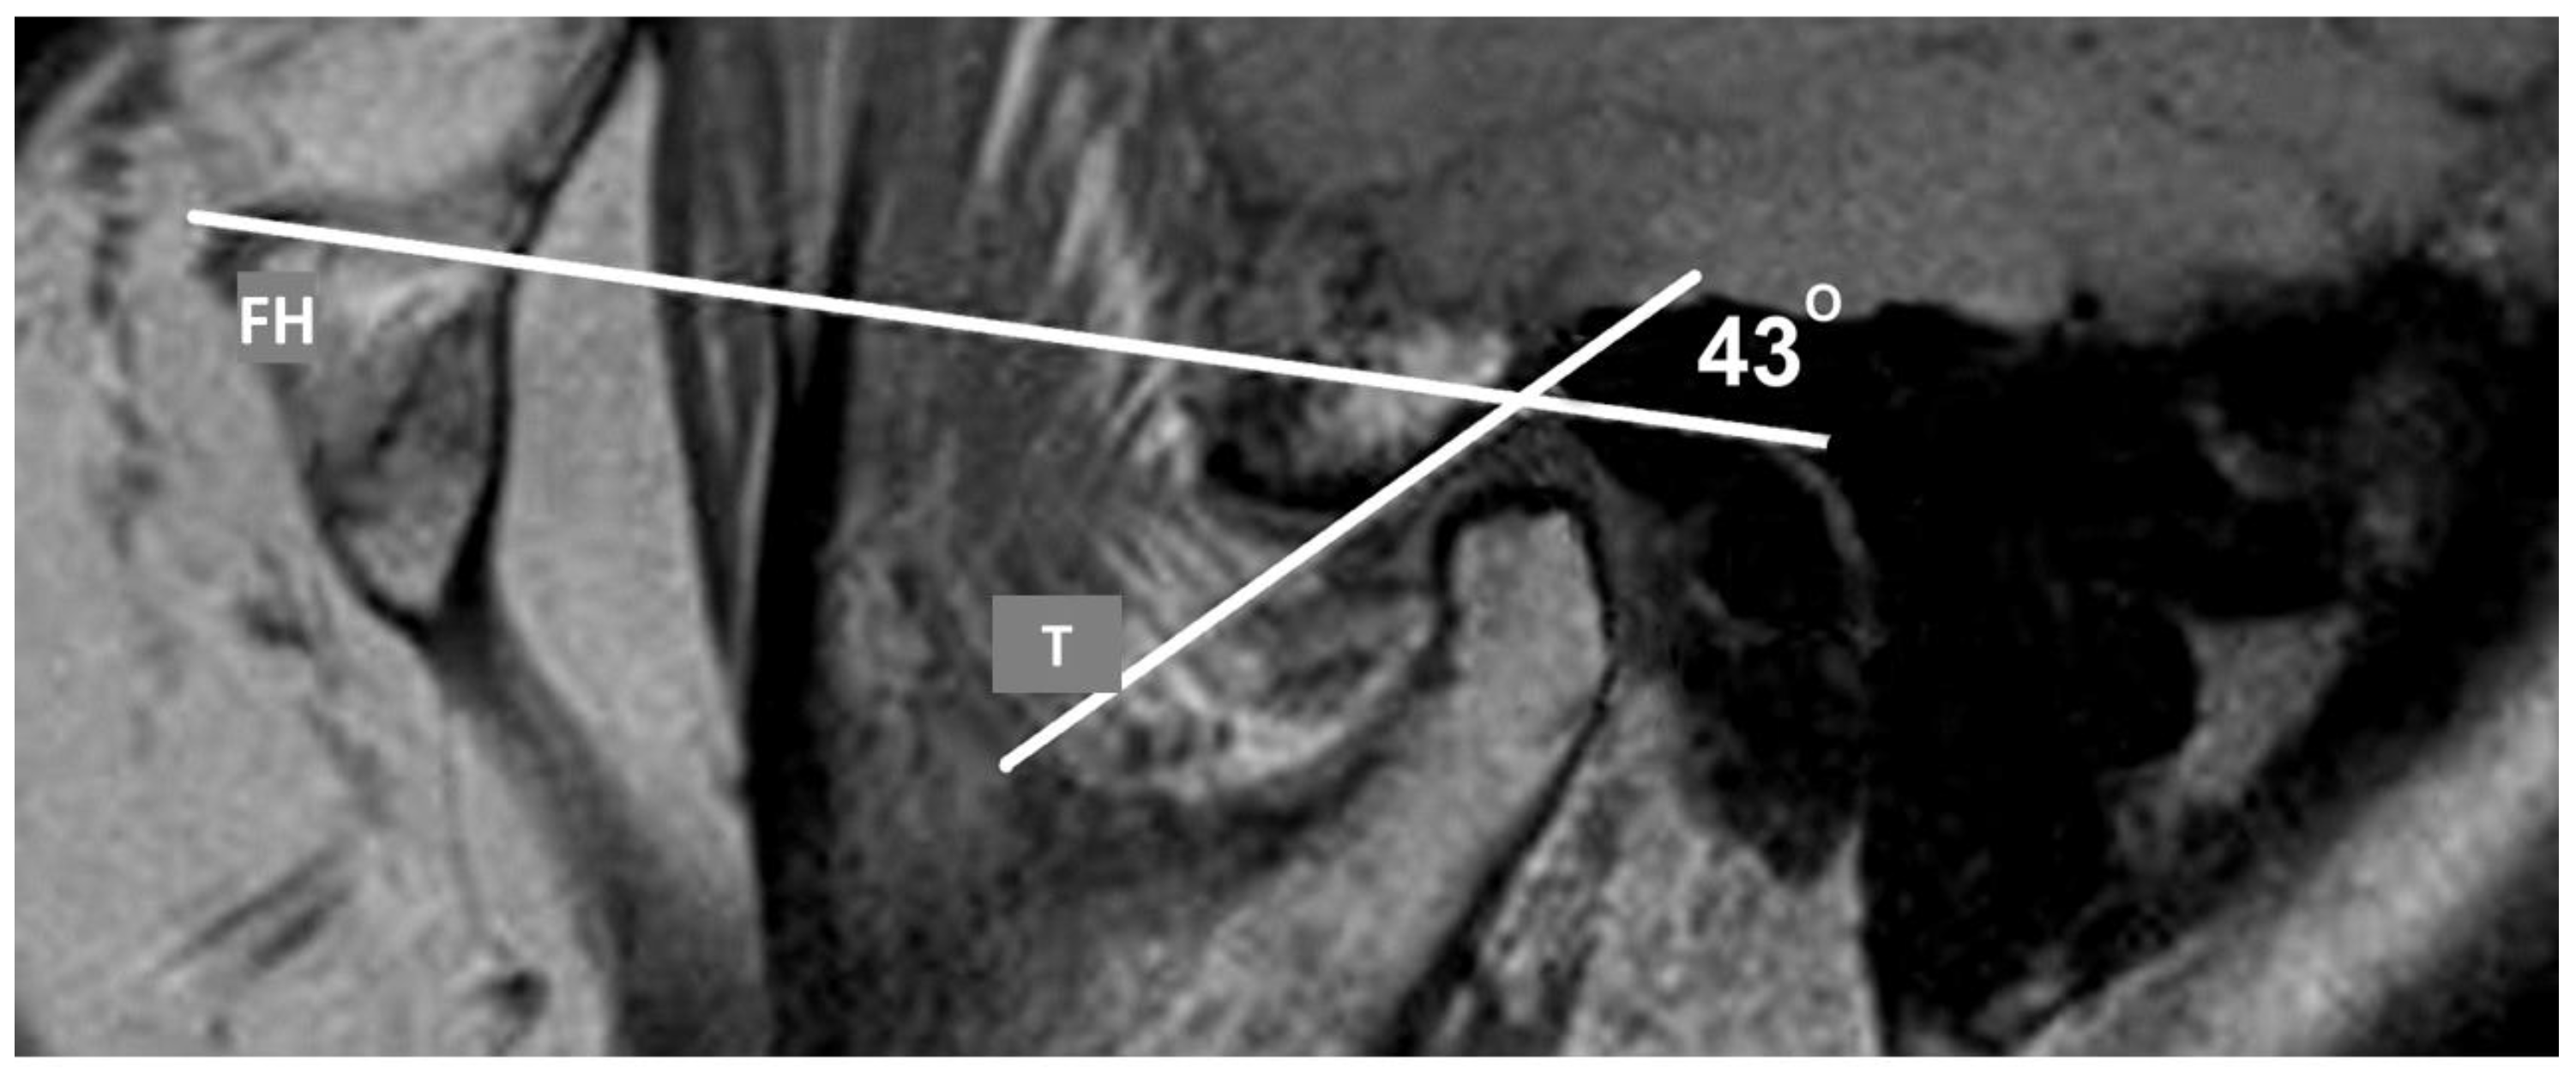

| Angle of articular eminence (o) | Normal | 145 | 46.36 | 6.37 | 31.00 | 64.00 | 0.531 | 0.589 |

| Anterior dislocation with reduction | 33 | 47.18 | 6.68 | 34.00 | 61.00 | |||

| Anterior dislocation without reduction | 12 | 48.00 | 5.39 | 39.00 | 55.00 | |||

| Total | 190 | 46.61 | 6.36 | 31.00 | 64.00 | |||